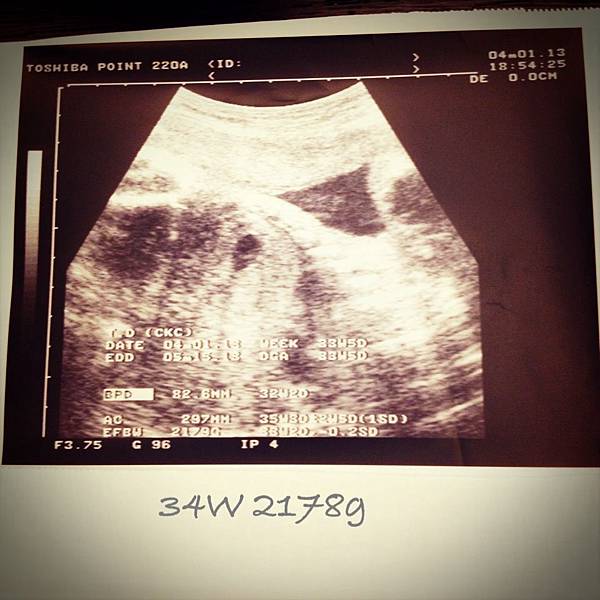

• 【媽咪日記】-即將進入卸貨階段~34週

34w

2013/04/01 Mon.(一)

~開始進入兩週產檢一次的旅程~

(繼續閱讀...)

文章標籤

佩姬 發表在 痞客邦 留言(0) 人氣(122)

• 個人分類:↖【幸せ】媽咪日記

▲top